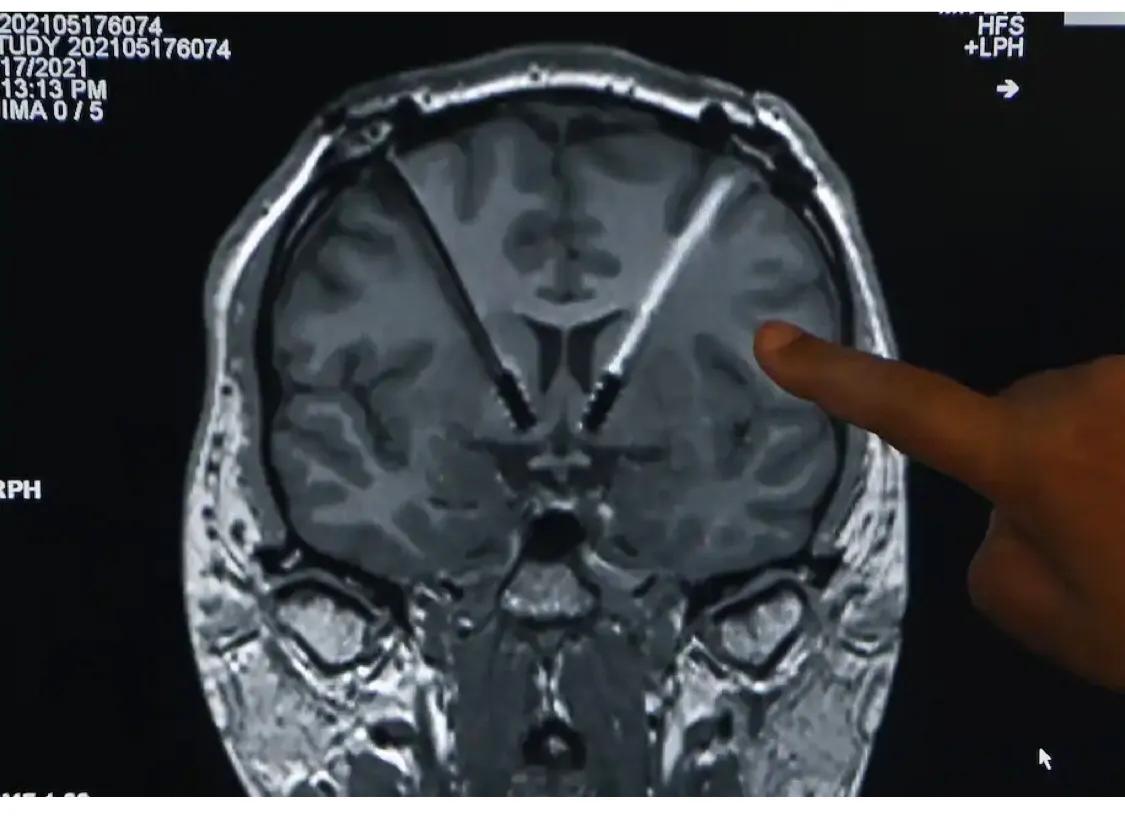

在7个小时的手术中,巴克哈尔特大部分时间都是醒着的,帮助医生在他的大脑中寻找植入物的精确位置。然后,雷扎将电线缠绕在巴克哈特的脖子上,与植入他左锁骨下的起搏器大小的刺激器相连。当巴克哈特把衬衫领口放下时,有一个明显的肿块,但他说,除此之外,他基本上没有意识到这个装置。

该设备的铂铱合金尖端每一个都有四个独立的接触点,允许医生在伏隔核的不同深度发射电脉冲。他们也可以调整电压,频率,极性和脉冲的时间,所有的用一个简单的平板。Buckhalter的持续清醒是通过尿检来证实的。

Buckhalter的大脑扫描显示了从他的胸部到颈部一直到大脑的电线。